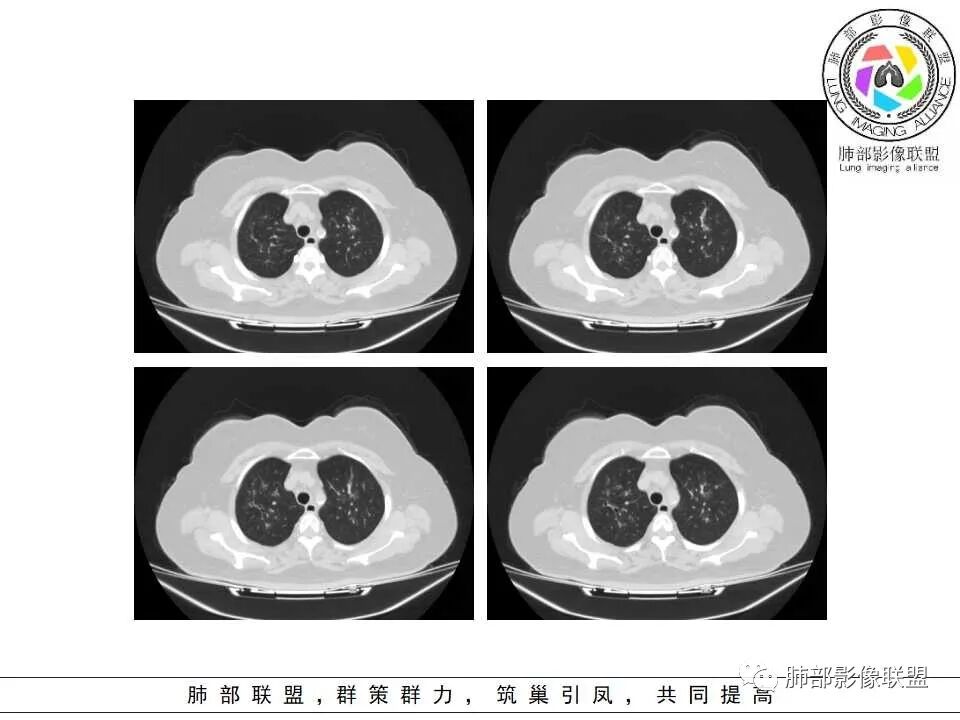

老年女性,糖尿病,高血压,心功能不全,双肺支气管壁增厚,沿支气管血管束分布结节状、片絮状模糊影,麻将馆、潮湿环境工作,考虑感染性病变,曲霉菌?

糖尿病,血糖控制不好,气促,炎症反应明显(白细胞,crp明显升高,Gm(+)。气道分布的结节磨玻璃密度影,树芽,气管壁增厚。曲霉的可能最大

两肺叶支气管壁增厚,边缘模糊,见多发树芽及腺泡结节,边界不清,非对称性分布,CRP和WBC显著增高,抗炎无效,急性过敏性肺泡炎,与曲霉菌鉴别。

老年女性,发现白细胞升高两年,此次入院多次查外周血白细胞>30*10^9/L,淋巴降低,CRP显著升高,但病程中无发热,以细菌性炎不好解释;CT提示有脾大,结合外周血象,首先考虑存在血液系统疾病(白血病)基础,且未系统诊治;肺部CT提示双肺中轴间质增粗,伴随支气管管壁增厚?多发树丫及腺泡结节,部分呈点晕征,可见肺动脉分枝增粗,一元论考虑白血病肺部浸润;二院论考虑白血病并发气道侵袭曲霉。以患者病程进展看,更倾向于白血病肺部浸润。

1.病灶沿支气管分布的特点相当明显,相应支气管壁广泛增厚。这种与支气管关系极为密切的片影和/或结节影,常高度提示气道相关感染,如支气管肺炎。

2.患者两肺多发病变,具有广泛性。如此广泛分布更多见于免疫低下的机会性感染。

3.支气管壁广泛增厚对气道侵袭性曲霉病具有一定的提示意义。注意患者没有支气管扩张,临床也未提供IGE等实验室资料。

4.老年女性患者,咳嗽少痰,伴喘息气短8天。注意患者没有发热,中毒症状不明显。既往糖尿病、高血压病史。

炎性指标升高,头孢等药物覆盖疗效不佳。

白细胞升高异乎寻常,注意病史已有两年之久,这至少提供两方面信息:

1)与本次肺部感染不能直接密切对应或相关联,能想象吗,这样的感染持续两年?

2)患者存在血液系统疾病的可能性,如白血病,这应当进一步查实。